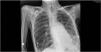

Our patient experienced clinical stagnation for 5 days due to complete atelectasis of the left lung. Non-invasive ventilation was alternated with high flow nasal cannula to maintain saturations at 90%. On the sixth day of clinical stagnation, the first respiratory physiotherapy intervention was performed. A pre- and post-radiological assessment was carried out. The recruitment of the left lung was clearly observed improving not only the radiological control but also the patient's symptoms and gasometric control, achieving PaO2/FiO2 values>300 within 24h. The respiratory physiotherapist's intervention had a significant impact on the patient's health, achieving the predefined goals prior to the session. Following clinical improvement, the patient was able to be transferred to their reference hospital within the next 48h, shortening their stay in the ICU (Figs. 1 and 2).